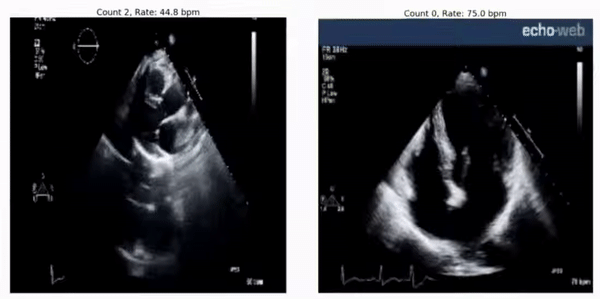

RepNet을 사용하면 심전도 비디오에서 심박수를 추정할 수 있습니다.

[그림 6] 예상 심박수 : 45 bpm (왼쪽) 및 75 bpm (오른쪽). 실제 심박수는 각각 46-50 bpm 및 78-79 bpm입니다. 여러 기기에서 발생하는 심박수에 대한 RepNet의 예측은 기기에서 측정 한 속도와 매우 유사합니다. (왼쪽오른쪽)